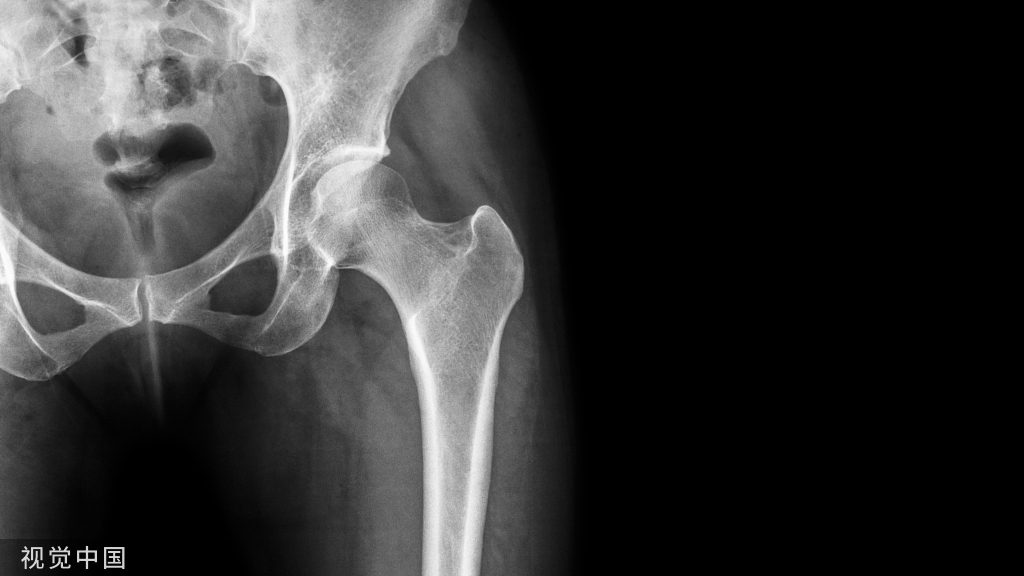

1. 临床资料患者,女,45岁,主诉因左上后牙不适1月来我院口腔科就诊。患牙不适1月,无自发性疼痛,无夜间疼痛,冷热刺激痛持续数分钟,咬合不适。无用药史,患牙未接受治疗。无药物过敏史。体检,无全身系统病史。患者口内黏膜正常,唾液分泌正常,全口重度牙周炎,牙龈广泛退缩,二度松动,A7冠修复。可见牙齿之间存在散在间隙,结石少量,仅存在上颌智齿。B6缺失,B7远中龋坏,探痛(+),冷热刺激疼痛,牙髓活力测试阳性。拍摄B7牙片,X线片可见B7远中邻面大面积低密度影像,与牙髓腔相通;仅一个根管位于牙根中央;根尖侧方暗影2 mm×2 mm低密度区域;近中牙周膜间隙增宽、远中牙周膜间隙模糊:牙槽骨水平吸收至牙根1/2处。因为B7牙髓仍存在活力,诊断为慢性牙髓炎。患者签署根管治疗同意书后进行B7根管治疗术。常规开髓,未用局麻药物,去除冠髓,仅探查一个根管口。在髓腔封三甲、置丁香油棉球、暂封,10天后复诊。期间无不适症状,去除暂封丁香油棉球及牙髓失活剂,次氯酸钠大量冲洗。10#K挫探查根管口,发现除中部存在一根管外,远中怀疑有一根管口并顺利进入。PropexII根管长度测量仪获得近中根管长度17.5 mm,远中根管始终显示超出根尖孔,按与近中根管同一长度将两个根管使用K挫扩大至25#,后使用Protaper手用器械扩大至F2(红)。根管内封根管消毒氢氧化钙、暂封,1周后复诊。患牙无不适症状。去除暂封及根管消毒材料,次氯酸钠大量冲洗。可见近中根管干燥、远中根管有渗出。插入牙胶尖示踪,可见近中牙胶尖位于牙体组织中央达到根尖部,远中牙胶尖位于远中牙周膜内。近中牙周膜间隙较术前变窄但仍宽于正常、根尖侧方暗影面积增大至3 mm×3 mm。(口腔学习平台 专注于牙科技术分享)根管内Vitapex封药2周复诊,患牙无症状。去除暂封后磨除远中无机釉及龋坏牙体组织可见一根管口位于根中部,另一根管位于无机釉质下方牙周膜处,有少量渗出,髓室底部破坏严重。在冠部远中用树脂形成假壁,光固化氢氧化钙及磷酸锌双重垫底,树脂修复患牙,降低咬合。X线片显示,根管恰填,位于根中部,冠部封闭,远中牙周膜间隙增宽,根侧方低密度影像模糊。未建议冠修复,不适随诊。